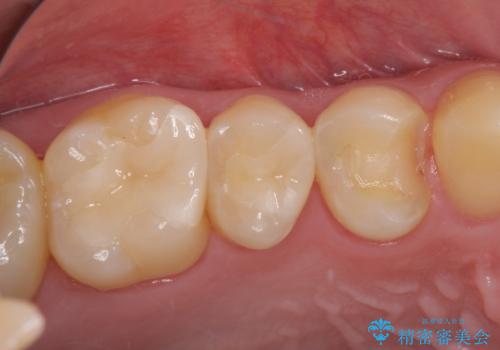

詰め物が外れた セラミックインレー修復

- 以前治療した詰め物が外れてしまい、冷たいものがしみることを主訴として来院された患者様です。

むし歯がないことを確認し、セラミックインレーにて修復するととしました。

適合の良いセラミックインレーの装着により、冷たいものがしみる症状はなくなりました。